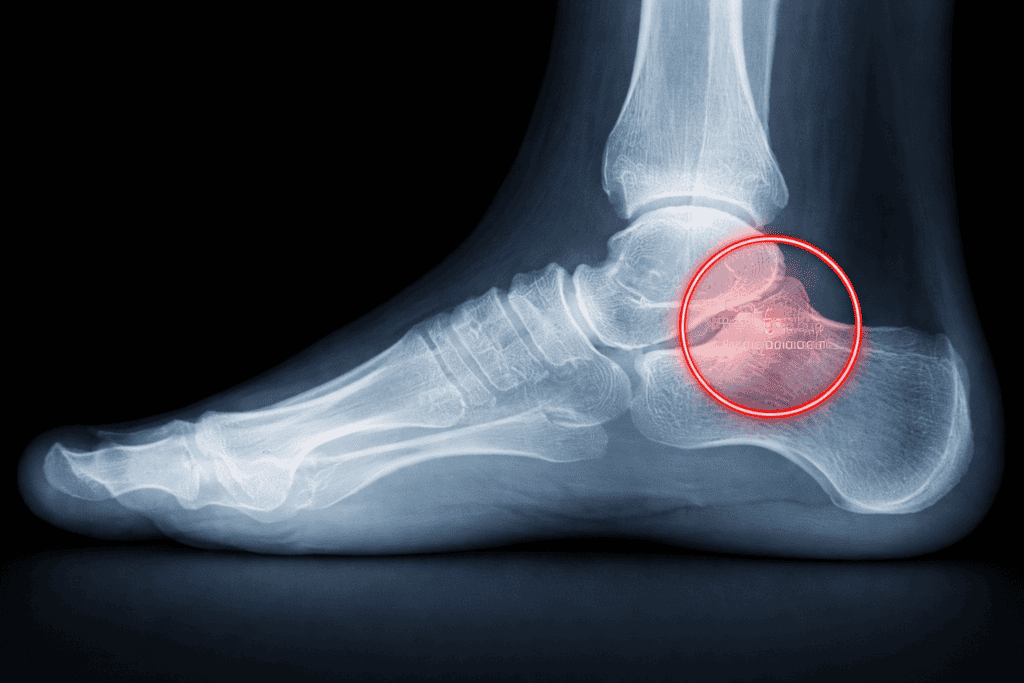

3. אבחון רדיולוגי (צילום רנטגן)

האבחנה המדויקת והחלטה על חומרת המצב מתבצעות לרוב בעזרת צילום רנטגן (X-Ray) הנעשה בעמידה (תחת נשיאת משקל).

בצילום נבחן שתי זוויות מפתח:

א. זווית מירי (Meary’s Angle): הזווית בין הציר הארוך של עצם הטאלוס לציר עצם המסרק הראשונה.

תקין: קו ישר או זווית של 0-4 מעלות.

פלטפוס: נוצרת "שבירה" של הקו כלפי מטה.

קל: 4-15 מעלות.

בינוני: 15-30 מעלות.

קשה: מעל 30 מעלות.

ב. זווית קלקנאל פיץ' (Calcaneal Pitch): מודדת את שיפוע עצם העקב ביחס לקרקע.

תקין: 18-30 מעלות (העקב "מתרומם" יפה).

פלטפוס: מתחת ל-18 מעלות. במצבים חמורים הזווית שטוחה או שלילית.